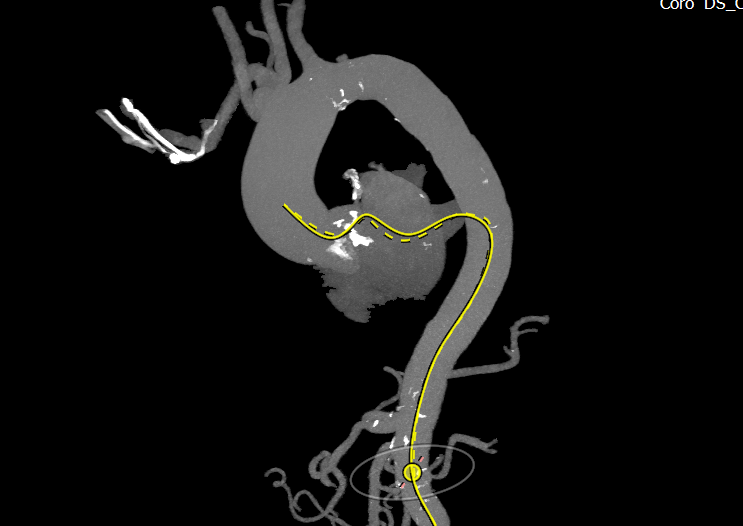

术前CT评估:

瓣环平均直径:26.8mm,左室流出道平均直径:31.2mm;

升主动脉(未见)明显扩张,心脏角度:69°;

左冠高度:12.5 mm,右冠高度:13.6 mm。

Annulus:26.8mm;LVOT:31.2mm

Sinus:27.4mm*40.7mm;STJ:32.9mm*32.9mm

升主:38.1mm*38.6mm;主动脉成角:69°

钙化积分:790